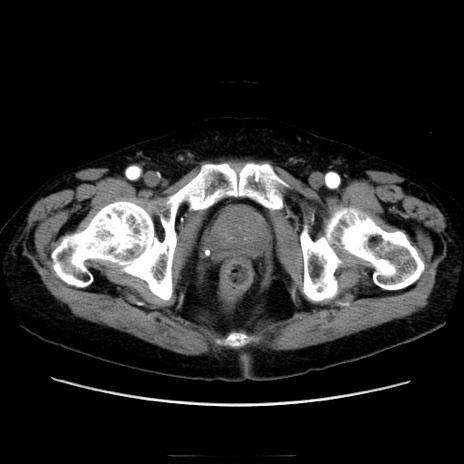

症例21(横断像)

【症例】70歳代男性

【主訴】腹痛

【現病歴】肝硬変・肝細胞癌にてかかりつけの方。約9時間前に食後より腹痛出現。症状が徐々に増悪し、嘔吐出現したため来院。

【既往歴】肝硬変、肝細胞癌(RFA、TACE後)

【身体所見】意識清明、表情苦悶様、BT 36℃、BP 129/78mmHg、P 88bpm、SpO2 97%(RA)、右上腹部から心窩部にかけて圧痛あり、反跳痛なし、筋性防御あり。

【データ】WBC 5800、CRP 0.16